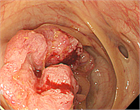

1. 大腸癌とは、大腸(盲腸、結腸、直腸)に発生する悪性腫瘍である。